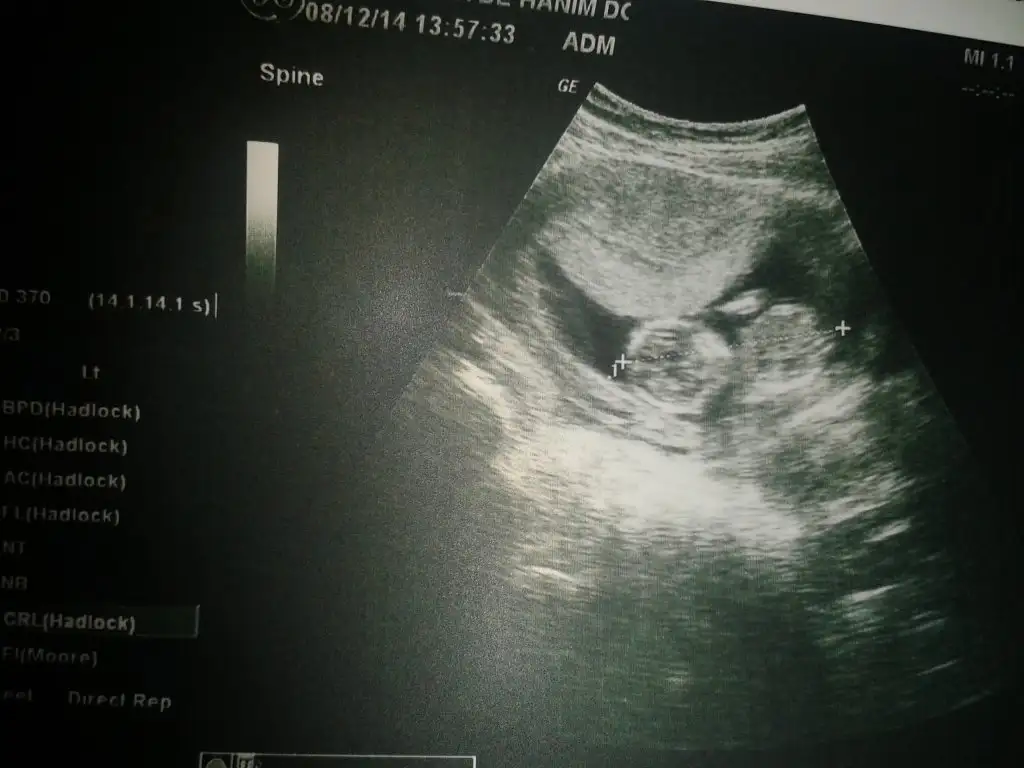

çok net olmasada erkek diyorum

bence erkekEki Görüntüle 1333927

Benimkinede bakarmısın arkadaşımbence de erkek, biraz soluk çıkmış ama. çıkıntı erkek gibi. :)

Ay cidden mibence erkek